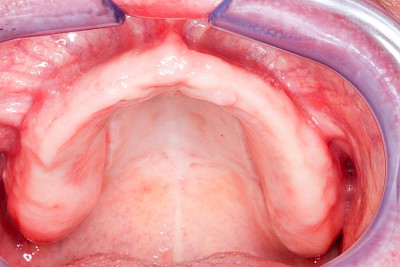

Überbeine im Bereich der Kiefer sind gar nicht so selten. Häufiger im Bereich der Seitenzähne unterhalb des Zahnfleisches, aber auch in der Mitte vom Gaumen. Überbeine haben in dem Sinne keinen Krankheitswert, müssen also nicht operativ entfernt werden, wenn diese nicht stören. Überbeine können ein Anzeichen für Knirschen und Pressen sein.

Gehen die Zähne verloren, baut häufig auch der Kieferknochen ab (Knochenschwund). Die Geschwindigkeit und das Ausmaß des Knochenschwundes ist von vielen Faktoren abhängig. Neben der genetischen Veranlagung spielen auch Überbelastungen in Folge, z. B. bei ständigem Knirschen oder Pressen, eine Rolle. Auch wenn Zahnprothesen Tag und Nacht getragen werden, kann die ständige Belastung der Schleimhäute und des Knochens den Knochenschwund beschleunigen.

In seltenen Fällen schwindet nur der Knochen, aber nicht die bedeckenden Schleimhäute. In diesen Fällen spricht man von einem sogenannten "Schlotterkamm".